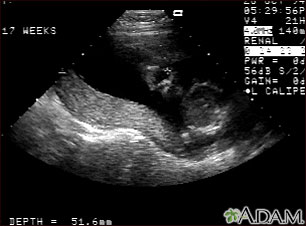

This is a normal fetal ultrasound performed at 19 weeks gestation. This ultrasound shows two interesting features. In the foreground, to the left and middle of the screen, you can see the placenta, following the curve of the uterus. In the background on the right, where the cross hair is pointing, you can see the face with all the facial features visible.